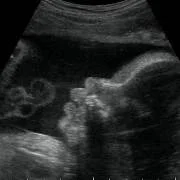

Onlangs had ik een hele leuke ervaring. Ik ben een gepensioneerd gynaecoloog, en was vroeger zeer begaan met mijn verloskundige patiënten. Mijn schoondochter en zoon nodigden mij uit om mee te gaan naar een "pretecho"van dr. Papa in Amsterdam. Wij, gynaecologen, hebben geweldige vooroordelen tegen een zogenaamde pret echo en vinden ze vaak overbodig. Nou dit pakte anders uit. We werden verwelkomd door een bijzonder charmante, leuke en vlot bespraakte Nederlandse Antiliaan: Elvin Papa, arts echoscopist. Daar zat hij in zijn spreekkamer, in een prachtig pand, achter een prachtig echo apparaat, dat voor mijn toenmalige ziekenhuis te duur was om voor ons gynaecologen aan te schaffen!! Alles werd getoond, het hele lichaampje van de baby. Alle organen, het geslacht, hart en bloedvaten noem maar op. Prettig was dat je in 3D een hele goede indruk krijgt van het gezichtje. Het hele onderzoek verliep voorspoedig en was heel relaxed. Papa doet veel aan nascholing en houdt de ontwikkelingen op echo gebied heel goed bij. Echo onderzoek kan heel vervelende zaken aan het licht brengen. Wij hadden een goed nieuws echo, dus dat is feest en lol. Belangrijk lijkt mij wel dat je met een slechte echo bij Elvin Papa in goede handen bent. Hij zal weten hoe je te troosten en hoe je door te verwijzen. Hopelijk hoeft dat niet vaak. Ik wens hem nog veel succes toe.

Als je zwanger bent wil je natuurlijk alles zo snel mogelijk weten over het kleine grote wonder wat in je lichaam groeit. En na veel leuke verhalen uit onze vriendenkring kwamen we samen met de familie, waar een prachtige ruimte voor is, terecht bij Dr. Papa, what’s in a name, voor een onbeschrijfelijke ervaring. Met heel veel geduld en tot in de kleinste details verteld Dr. Papa dat we een zoon verwachten, en nog belangrijker, dat alles er op en er aan zit. De beelden die die haarscherp op de grote schermen te zien zijn met daarbij de haarfijne uitleg over de complete anatomie van onze zoon maken deze dag tot een onvergetelijke ervaring. Als er een Nobelprijs was voor de leukste dag, dan was die voor Dr. Papa. Heel veel dank Dr. Papa!

Nooit gedacht dat het zo leuk zou zijn om een pretecho te laten doen. Het is ongelooflijk wat je kunt zien. Dit komt te meer omdat drs Papa de tijd neemt en uitgebreide informatie geeft. Ineens krijg je een beetje een beeld bij wat er in je buik zit en dat is zo gedetailleerd dat je zelfs al gelijkenissen ziet met moeder of vader. Daarnaast krijg je de beelden mee op DVD. Zou ik graag van mezelf hebben gehad!